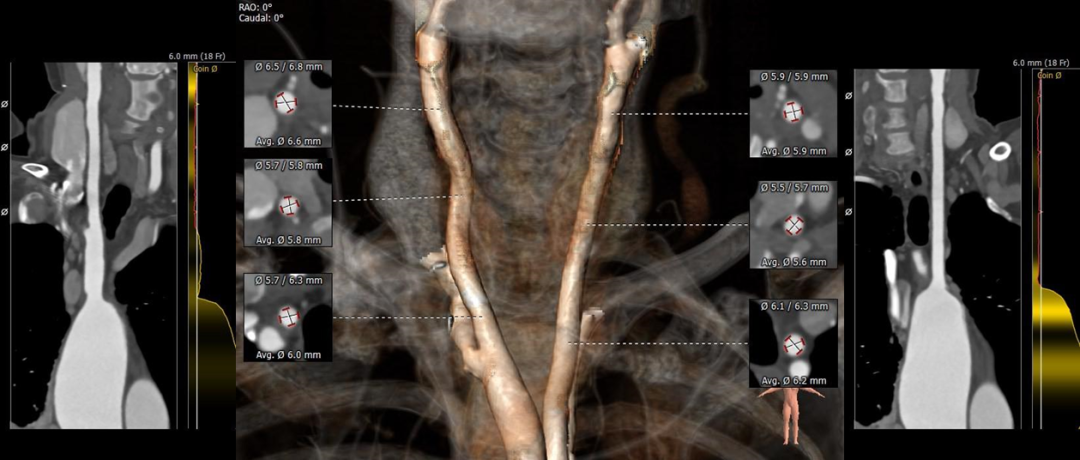

主动脉根部测量:

三叶式瓣,瓣叶增厚,可见钙化融合,非横位心。

冠脉测量:

右冠开口高度可左冠开口偏低(11.5mm),左冠窦瓣叶冗长(16.1mm)。

左室测量:

左室心肌肥厚,收缩期内径显著偏小(17.7*21.2mm)。

弓部及入路:

弓部宽度角度可,股髂血管纤细(左髂最窄处4.4mm,右髂最窄处4.3mm)。